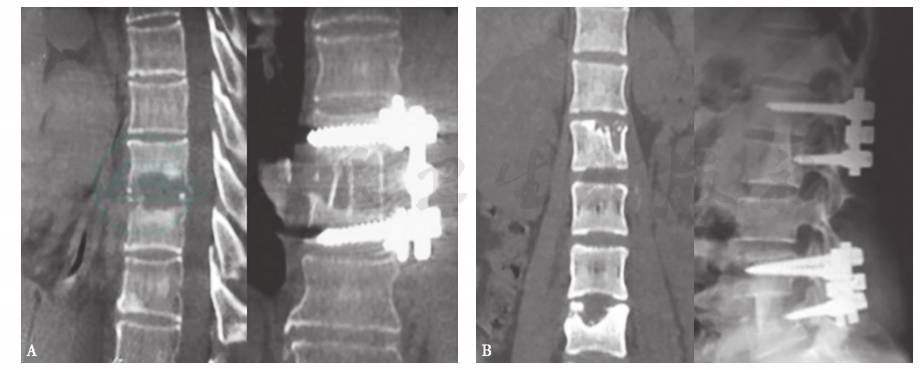

脊柱结核占全身骨关节结核的首位,该病起病隐匿,进展缓慢,临床症状不典型,存在较高的漏诊或误诊率,如果治疗不及时,将引起严重的腰背部疼痛、脊髓神经功能损伤、冷脓肿形成、后凸畸形、椎体不稳,甚至瘫痪。给患者带来沉重的精神和经济负担。及时、有效地彻底清除结核病灶、恢复脊髓功能、重建脊柱稳定性和早日康复对于脊柱结核的治愈至关重要。目前对出现脊柱不稳或畸形、出现神经压迫或瘫痪的患者,在彻底病灶清除、椎管减压、畸形矫正、植骨融合的基础上,采用器械内固定,使得脊柱结核的治疗进入新纪元(图4)。

图4脊柱结核采用彻底病灶清除、椎管减压、畸形矫正、植骨融合及器械内固定

A.前路内固定;B.后路内固定。